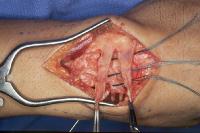

Complete scapholunate ligament disruption seen intraoperatively. A strip of extensor retinaculum is harvested as a ligament graft, left attached to the triquetrum. (Right hand, fingers to the right)

Click for larger image